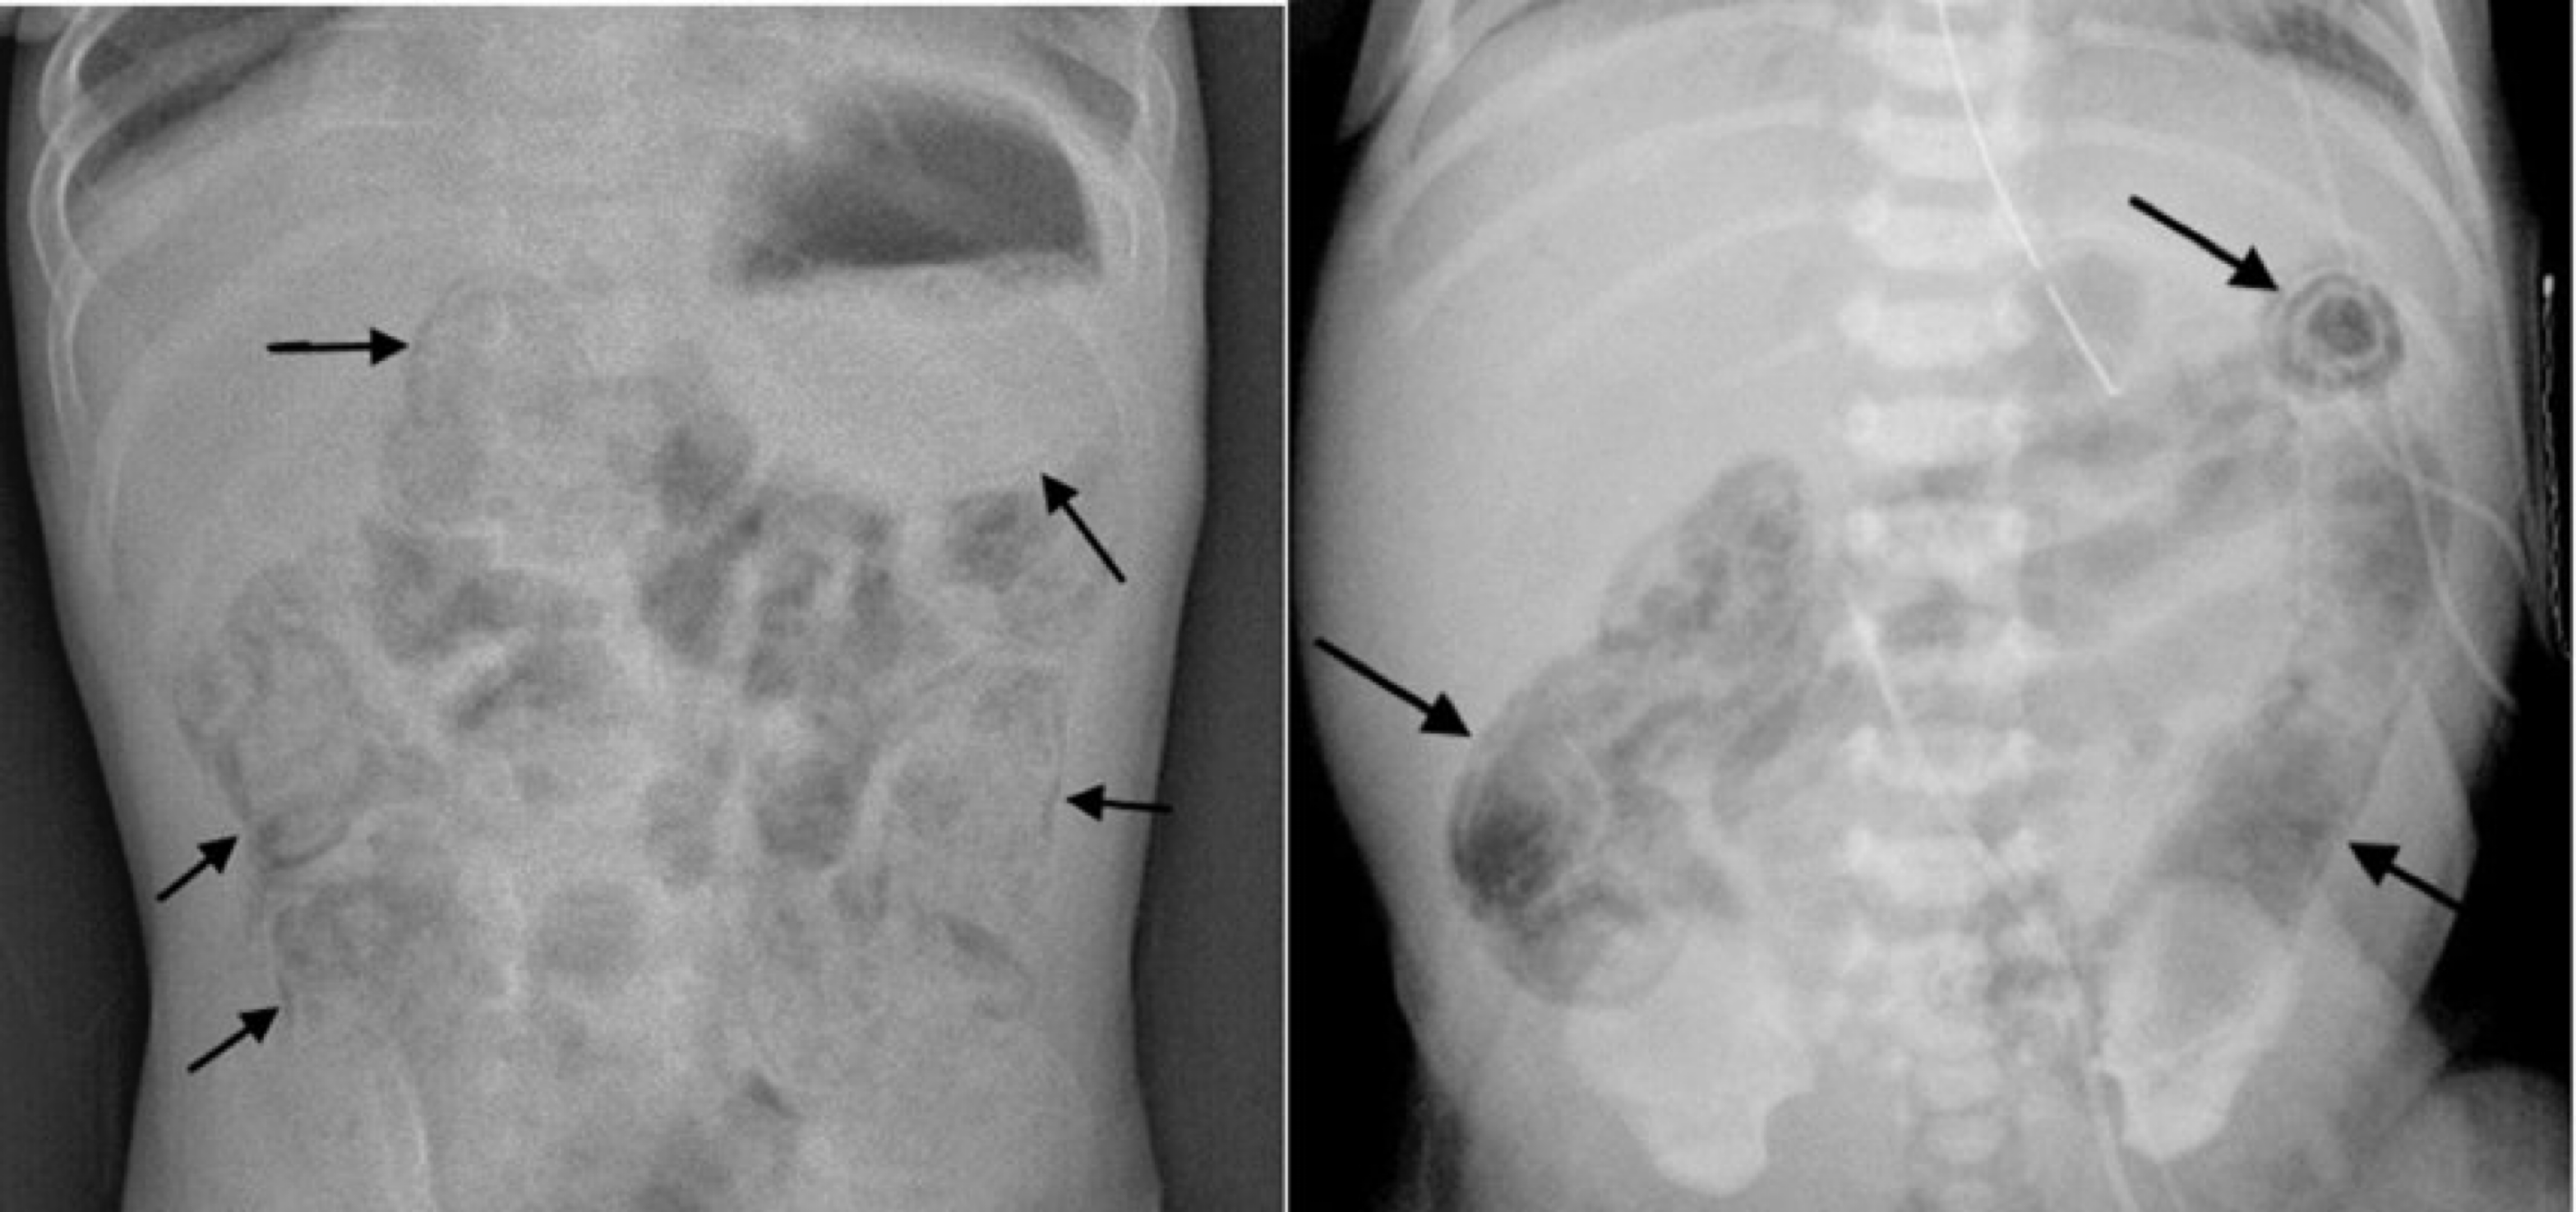

• pneumatosis intestinalis (intramural bowel gas)

: 방사선 검사 상 장 벽 내부에 공기음영이 보이는 소견 (장벽의 괴사를 시사)

• portal vein gas

:NEC가 진행되면 장벽 내의 가스가 혈관으로 들어가 간문맥을 따라 공기음영이 확인

• pneumoperitoneum